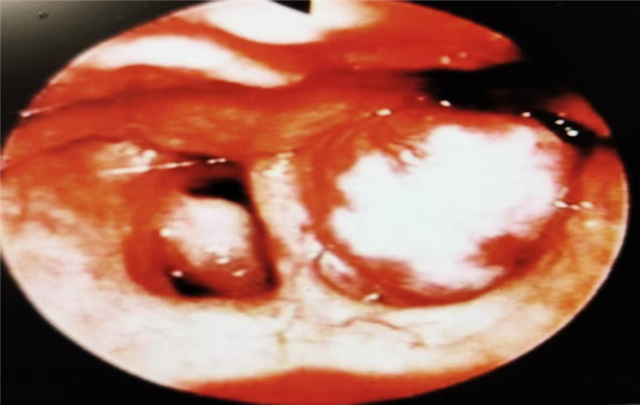

图片1:鼻咽镜下左侧鼻咽顶鼻咽纤维血管瘤表现(图片来源于百度)

目前主要通过鼻内镜或者电子鼻咽检查予以初步诊断,最终依赖于鼻咽部CT和MRI来术前诊断。